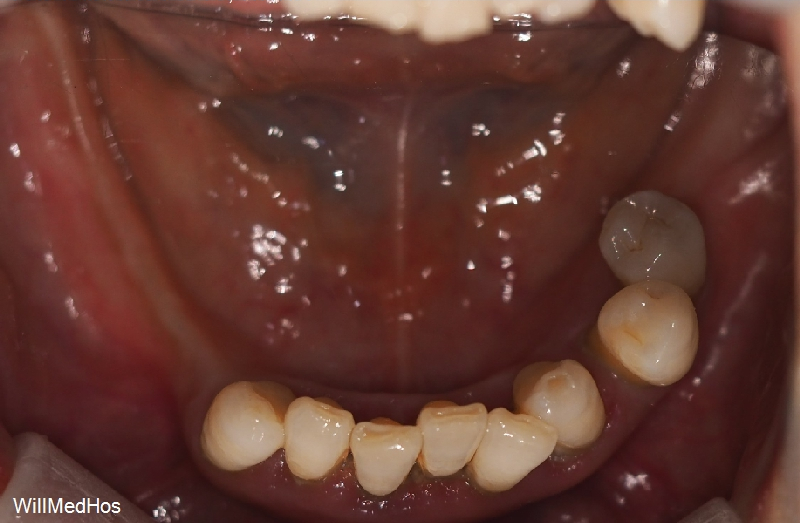

오늘 말씀 드릴 환자분은 10년 가까이 치과에 오시지

않으시다가 내원 해주신 환자분 입니다.

환자분의 초진 구강 사진부터 보도록 할께요.

이미 자연 발치와 치과에서 발치 진단을 받으시고 발치 후 10년 가까이 치아들을

방치 해놓으신 상태라 위의 치아들이 정출되어 내려오기도 하고 관리가 아예 안되신 상태 이셨습니다.